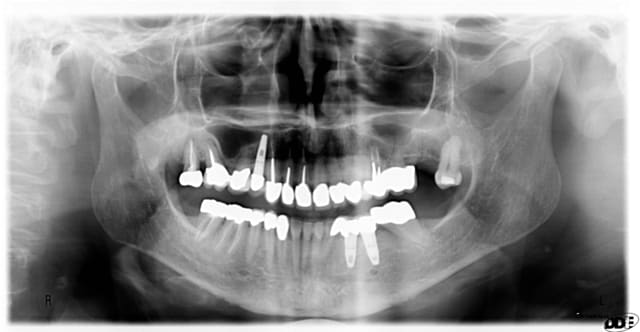

2 e8z5kj - Eugenol

3 ynnt5o - Eugenol

1 d1vreh - Eugenol

4 r3f3ot - Eugenol

Cas similaire, mais sans érosion en pré-op, seulement attrition et perte de DVO. D'après moi, un patient bruxeur restera bruxeur....

après quelques traitements endodontiques, l'accord de la patiente pour couronnes en or complètes en postérieur; quasi indestructibles...et quelques implants pour les zones édentées..